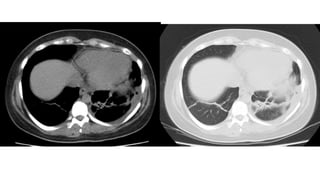

Hallazgos atípicos en TC de TX - Complicaciones

●Linfadenopatía mediastínica

●Derrame pleural

●Nodulillos centrolobulillares

●Patrón de árbol en brote

●Engrosamiento de la pared bronquial

●Cavitación

●Neumotórax

Neumomediastíno

Neumotórax

TEP